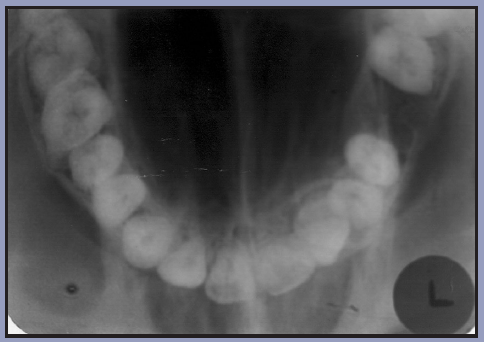

Figure 3 – Occlusal Images

Figure 3

Occlusal radiography is a supplementary radiographic examination designed to provide a more extensive view of the maxilla and mandible.

The occlusal image, as seen in Figure 3, is very useful in determining the buccolingual extension of pathologic conditions, and provides additional information as to the extent and displacement of fractures of the mandible and maxilla. Occlusal radiographic images also aid in localizing unerupted teeth, retained roots, foreign bodies, and calculi in the submandibular and sublingual salivary glands and ducts. It should be noted that when imaging soft tissues, exposure time needs to be appropriately reduced.